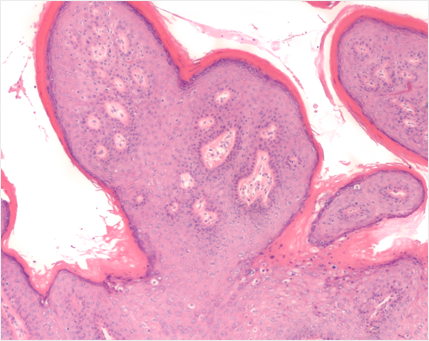

콘딜로마

Condyloma

인유두종 바이러스(HPV)가 원인으로

성기나 항문 주변에 닭벼슬 모양으로 번지는 사마귀

약물 치료나 레이져, 혹은 고주파 치료로 쉽게 치료가 되는 반면

근본적인 원인 치료가 안되기 때문에 재발이 잘 됩니다.

최근에는 HPV 백신 접종을 통해 예방이 어느 정도 가능합니다.

콘딜로마가 생겼다면 즉시 치료를 받아야 하는데 자궁 경부에 고위험군

HPV 감염이 있을 경우는 자궁경부암을 일으킬 수도 있으므로 반드시 HPV검사 및

자궁 경부 세포진 검사를 받고 향후에도 정기적인 산부인과 검진

을 받아야 합니다.